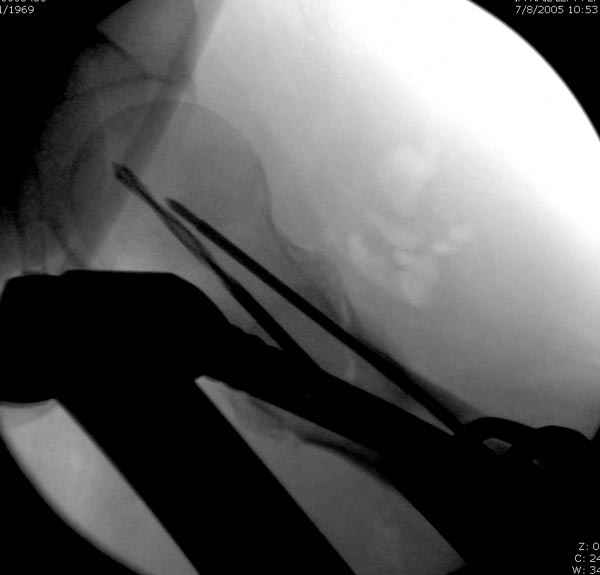

Как раз недавно у меня был примерный случай: больному 36 лет, поступил ночью, травма в результате мотоциклетной аварии, кроме чрезвертельного и спирального перелома левого бедра имеется переломы костей предплечья с этой же стороны. Скелетное вытяжение, а на следующий день больной про оперирован на ортопедическом столе с дистракцией. Чтобы не расколоть чрезвертельный перелом провели временную спицу ближе к переднему кортексу, из малого разреза костодержатель для репозиции, а фиксацию провели антиградным штифтом. Этапы операции на снимках.